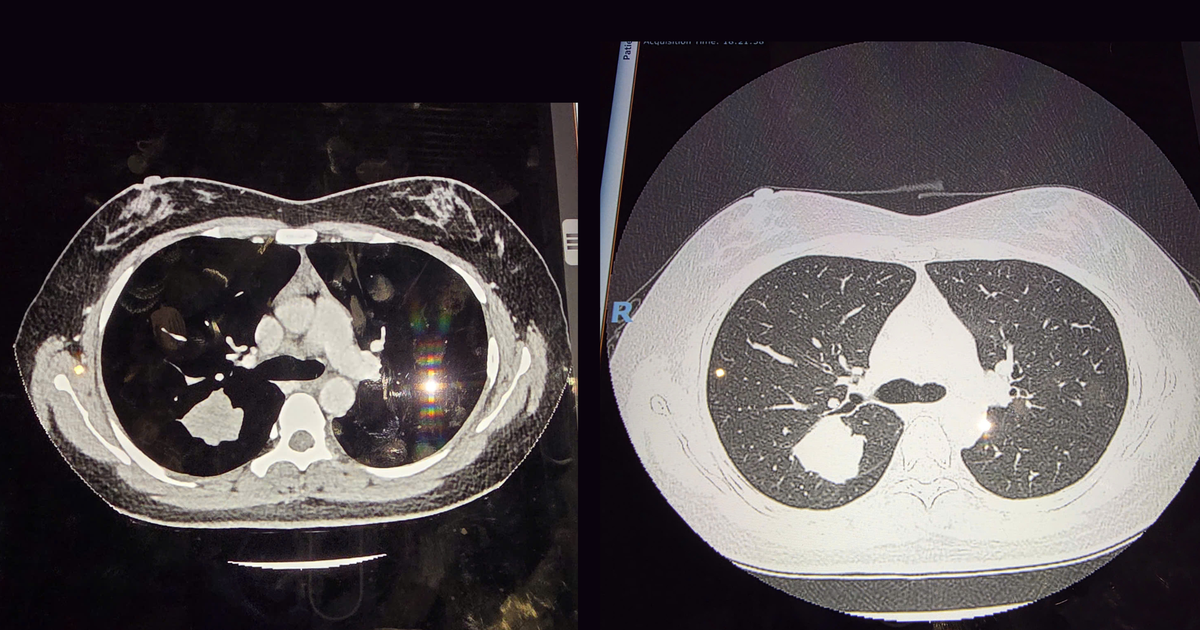

Bà Lan được phát hiện nốt mờ khoảng 10 mm thông qua chụp CT VnExpress. Các bác sĩ đánh giá đây là tổn thương ác tính giai đoạn sớm VnExpress. Để xác định chính xác, các bác sĩ đã tiến hành sinh thiết bằng phương pháp nội soi lồng ngực VnExpress. Kết quả giải phẫu bệnh khẳng định đây là ung thư phổi biểu mô tuyến, độ 2 VnExpress.